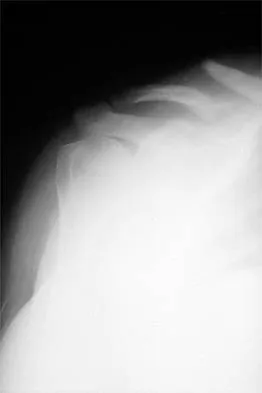

Figures 10a and 10b show the radiographs of a 47-year-old man who reports pain in both shoulders. He has a history of leukemia that was treated with chemotherapy and high-dose cortisone. What is the most reliable treatment option for pain relief in this patient?

Explanation

The radiographs reveal osteonecrosis with collapse. The most reliable and durable treatment for osteonecrosis of the humeral head remains prosthetic shoulder arthroplasty. Osteonecrosis of the humeral head may be seen after the use of steroids, and there is an increasing demand for shoulder arthroplasty in young people because of the use of high-dose steroids in chemotherapy regimes for the treatment of malignant tumors. The indications for most shoulder arthrodeses today include posttraumatic brachial plexus injury, paralytic disorders in infancy, insufficiency of the deltoid muscle and rotator cuff, chronic infection, failed revision arthroplasty, severe refractory instability, and bone deficiency following resection of a tumor in the proximal aspect of the humerus. Clearly, the role of arthroscopy and related minimally invasive techniques in the treatment of humeral head osteonecrosis remains unknown. Hasan SS, Romeo AA: Nontraumatic osteonecrosis of the humeral head. J Shoulder Elbow Surg 2002;11:281-298. Hattrup SJ: Indications, technique, and results of shoulder arthroplasty in osteonecrosis. Orthop Clin North Am 1998;29:445-451.